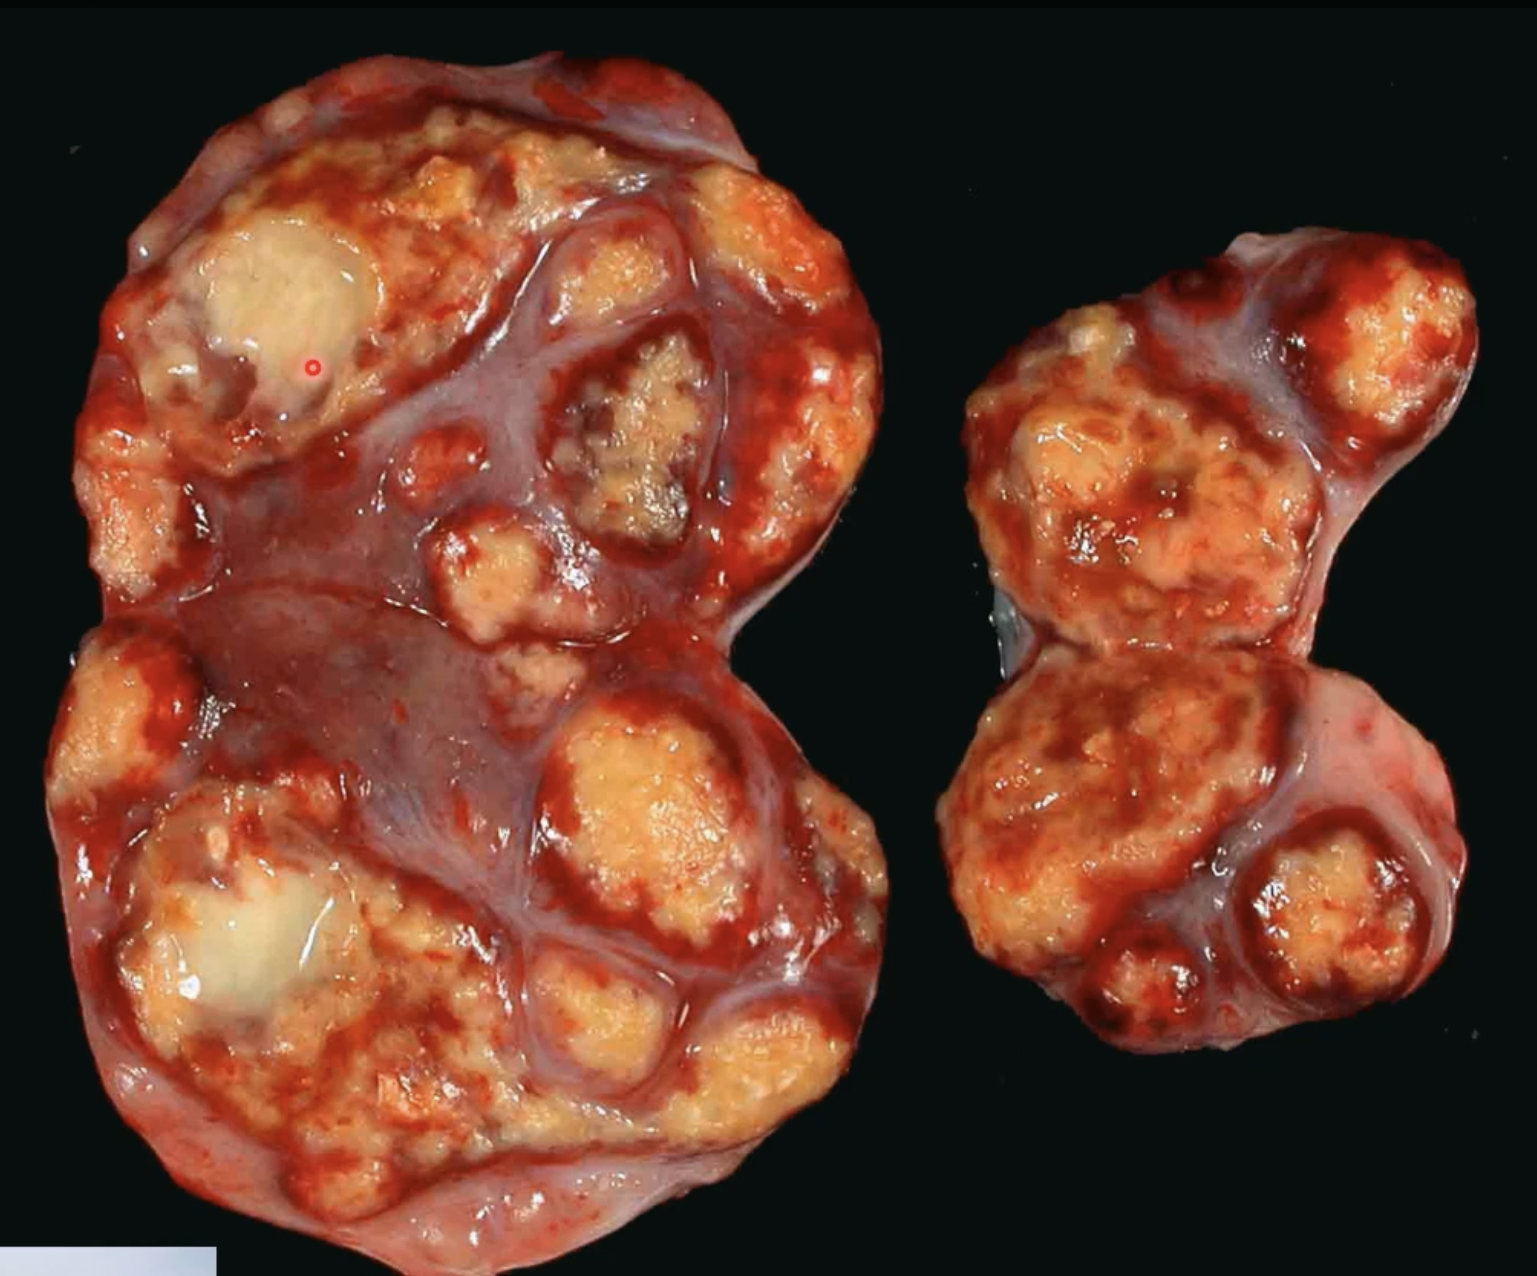

lymphoid effaced by cheese-like material - caseous necrosis

what is happening

lymph node in goat - caseous lymphadenitis, effaces normal tissue and white areas are gritty - caseous necrosis

large glomerulations of macrophages - caseous necrosis